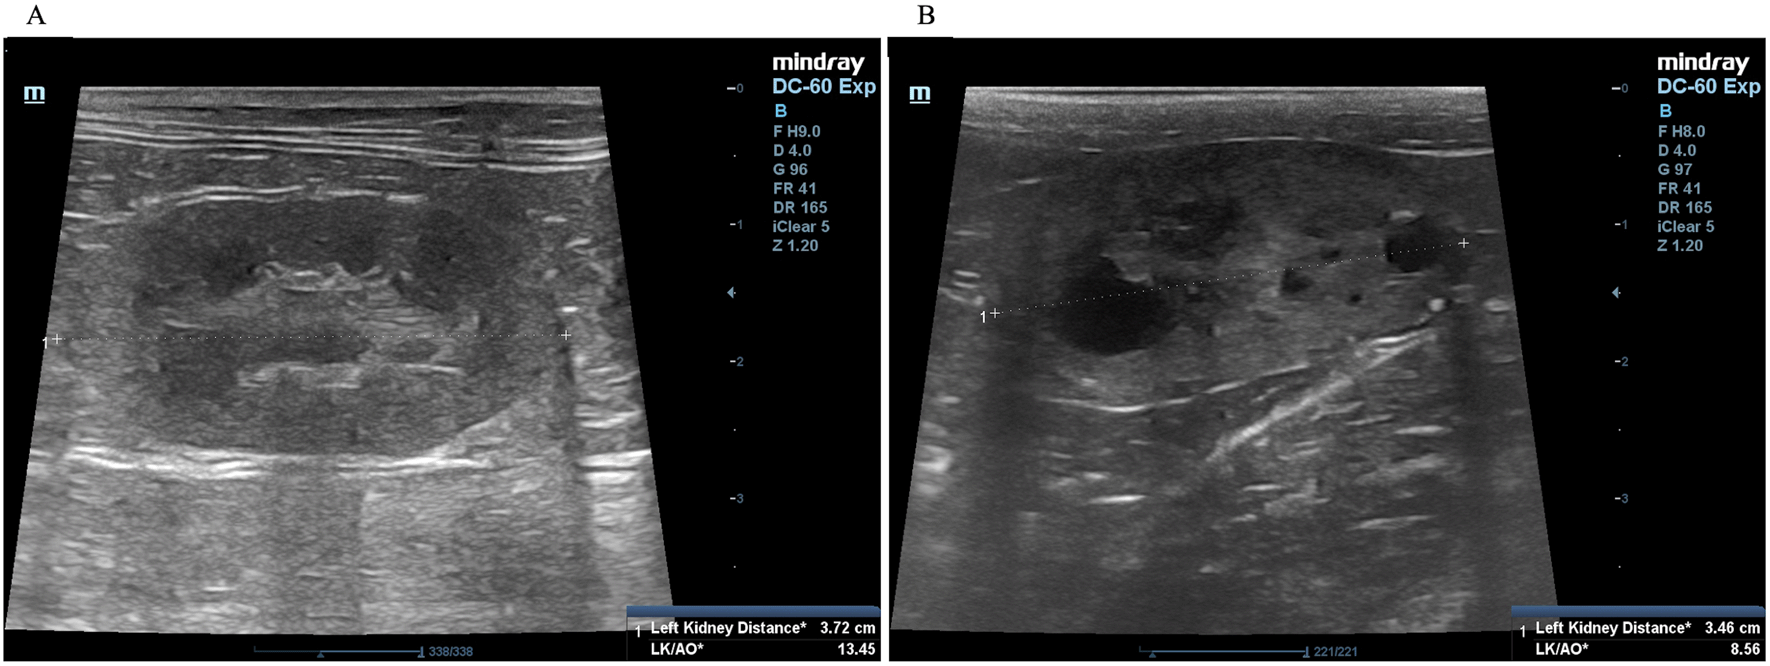

A complete blood count and serum biochemistry profile were performed for each cat. Kidney characterization was assessed by ultrasonography analysis in all cats using only gentle restraint and no sedation. In our ultrasonographic examination, all cats were clipped the hair at the abdominal area and the ultrasonographic gel was utilized in all cats. The non-invasive two-dimensional (2D)-mode ultrasonography was used to define the kidney structure and size. The ultrasonography images have demonstrated that multiple cysts are a common finding in PKD1 heterozygous mutation cats, as shown in Figure 2.

The procedure for ultrasound examination of the kidneys followed that of a previous report.4,20 Briefly, ultrasonography was performed using a Mindray real-time ultrasound machine (model DC-7, Shenzhen Mindray Bio-medical Electronics, Nanshan, Shenzhen, China) with a linear transducer (frequency 7.5-12.0 MHz). The kidneys were examined in the longitudinal and transverse planes. Results were recorded for each cat. The three separated regions, the renal cortex, the renal medulla, and the renal sinus, were identified. The renal sinus is the most hyperechoic component of the kidney and is surrounded by the renal pelvis and vascular branches. In the renal pelvis, ultrasonography images can be assessed using the renal crest as a landmark. The renal size can be measured by measuring from the long axis view. The renal lengths of the right and left kidneys were measured to identify the renal structure, as shown in Figure 2.

The association between ultrasonography findings and the genotypes of PKD1 mutations was analyzed for 108 cats. PKD1 heterozygous mutations were identified in 21 cats, and the results showed significant differences between C/C and C/A genotypes for the homozygous wild-type and heterozygous mutation (Figure 4). In the present study, gene mutation cats were associated with cyst formation in cats. The ultrasonographic analysis showed renal cysts in 19 cats, and all of these cats harbored PKD1 heterozygous mutations. However, there was a 51-month-old domestic shorthair cat without the PKD1 gene mutation developing the cysts in renal parenchyma. Table 3 demonstrates the number of cats in various breeds with PKD1 gene mutation and renal cyst development.

Regarding renal ultrasonography, the effectiveness of this method was evaluated for detecting the variation of PKD1 gene polymorphism (Table 4). The sensitivity and specificity of renal ultrasound accounted for 100.00% (95% CI, 84.54 to 100.00) and 98.91% (95% CI, 94.10 to 99.94), respectively. In addition, positive predictive value (PPV) and negative predictive value (NPV) were indicated at 95.45% (95% CI, 78.20 to 99.77) and 100.00% (95% CI, 95.95 to 100.00), respectively. On top of that, according to the OD, presenting renal cysts from renal ultrasonography increased the possibility for PKD1 heterozygous mutation 2,623.00 times (95% CI, 103.2465 to 66637.8792, P < 0.0001).